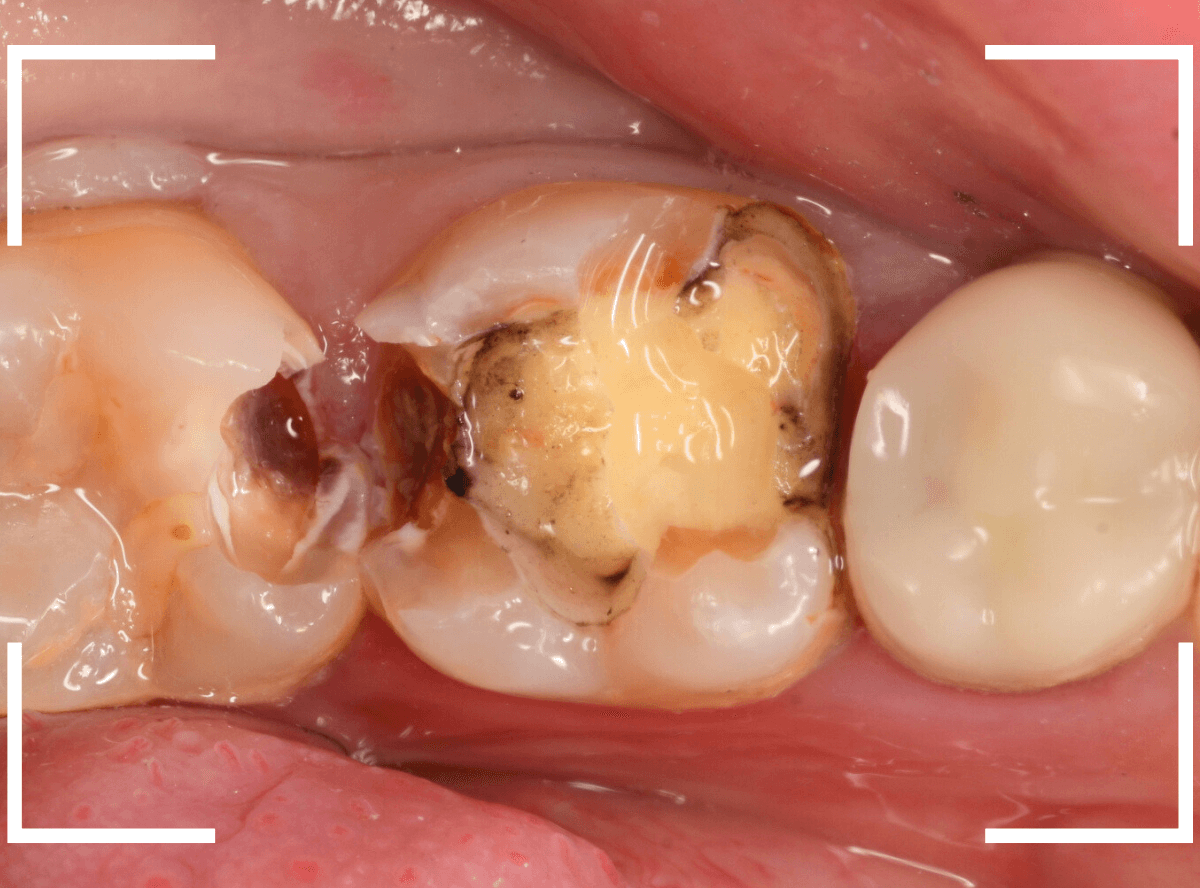

Case.25 レントゲン所見と目視を頼りに、虫歯治療

検査時に〇部、歯と歯の間の小臼歯部に虫歯らしき黒い影があるのが見つかりました。

かなり怪しいですが、メタル・インレーが入ってるので、それが透けている可能性もあります。

レントゲン写真で確認します。

レントゲンでは後ろの大臼歯部の方が虫歯になっているように見え、小臼歯部は問題ないように見えます。

まず大臼歯のインレーを外して、中を調べます。

あれ、インレー直下は虫歯がなさそうです。

レントゲン写真を頼りに、歯を削ると、虫歯が出てきました。

大臼歯の虫歯を削っていくと、手前の小臼歯まで虫歯がつながっていました。

やはり、黒い影は虫歯でした。これは深そうです。

メタル・インレーも外して、虫歯を除去します。

全ての虫歯を除去しました。

レントゲン写真では確認できませんでしたが、手前の小臼歯は深い虫歯でした。

このように、歯と歯の間の虫歯は、深い事が多いです。